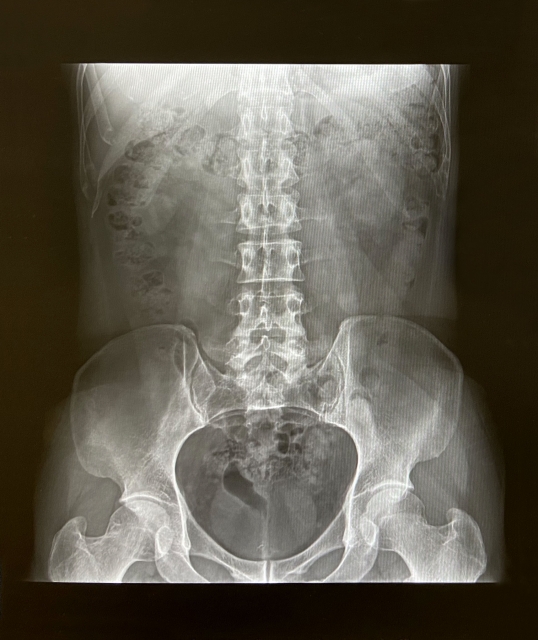

腹部レントゲンでうつるもの

レントゲンは体にX線を当てて、そのX線がどのくらい体を通りやすいかで色合いが変わり、現像されます。

- X線がよく通る=フィルムや検出器にたくさん届く→黒く映る

- X線が通りにくい=フィルムや検出器に届かない→白く映る

- 黒く映る:空気が代表

- 白く映る:骨、人工物(金属)、造影剤(バリウムなど)が代表

- 筋肉や脂肪分など:少しX線を吸収するのでその場所の成分によって、濃淡がつく

おなかの場合

- 骨・バリウムなどの飲んだ造影剤がある、大きな硬い石(胆石など)=白

- 胃、腸の中の空気=黒

- 肝臓や腎臓、筋肉、脂肪など=濃淡のあるグレー

これらが一枚の写真の中にうつっていることになります。

腹部レントゲンの写真からわかること

白くうつるものから

特に造影剤を飲んでいないと仮定すると、白くなっているのは骨です。

背骨と骨盤になります。腹部症状とは大きくは関係ない部位です。